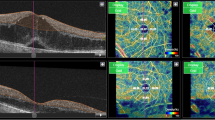

The anatomical features of SSPiM on OCTA were noted. SSPiM signals were localized to the FAZ margin (vascular/avascular junction) or center. SSPiM was associated with corresponding hyperreflective fluid in all cases. SSPiM was also associated with hyperreflective material in 34 eyes (89.5%). The SSPiM-related hyperreflective fluid was located in the outer nuclear layer adjacent to the outer plexiform layer in 31 eyes (81.6%) and in the inner nuclear layer in seven eyes (18.4%) (Fig. 1).

SSPiM appearance in two different cases. Case 1: A 58-year-old man with type 2 DM for 20 years. a On the outer retinal slab of en-face OCTA (upper left), the pseudo-flow signal extending from the center of the FAZ to the periphery is indicated with a white arrow. b Cross-sectional B-scan OCT image with superimposed OCTA flow signal (lower left) shows hyperreflective fluid with no hyperreflective material at the margin and a nonvascular pseudo-flow signal shown in red (white arrow), as well as hyporeflective fluid with no flow signal (yellow arrow). Case 2: A 53-year-old man with type 2 DM for 15 years. c On the outer retinal slab of en-face OCTA (upper right), the pseudo-flow signal extending from the center of the FAZ to the periphery is indicated with a white arrow. d Cross-sectional B-scan OCT image with superimposed OCTA flow signal (lower right) shows hyperreflective fluid accompanied by hyperreflective material and a nonvascular pseudo-flow signal shown in red (white arrow), as well as hyporeflective fluid with no flow signal (yellow arrow)